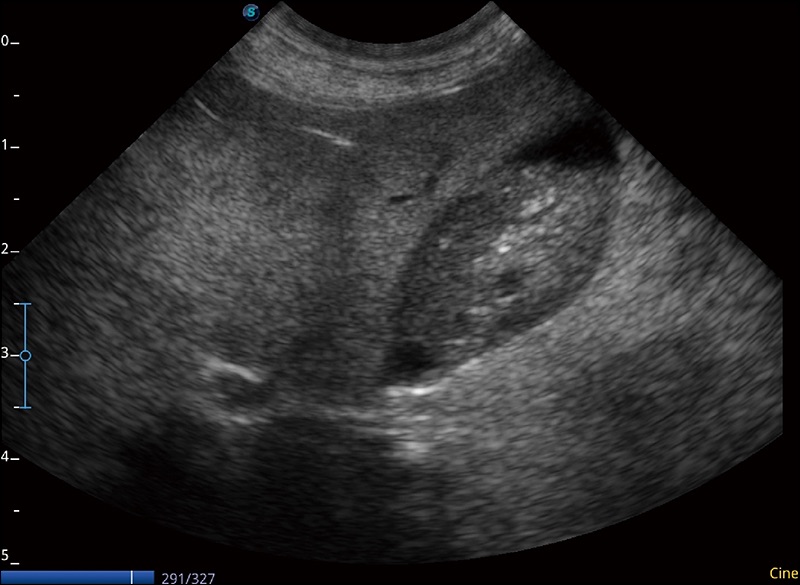

α1卓越的图像质量和便捷的工作流程,使每位宠物医生都能轻松扫查。其全面的兽用应用功能和紧凑型的结构设计,可以满足动物检查的多种需要。专业的预设检查模式和多领域测量软件包有助于为不同类型的动物提供检查, 让宠物医生能够出色的完成工作。

人机工程学设计

15.6英寸高清显示器

灵活可调节的显示器

防水面板设计

快速启动

静音系统